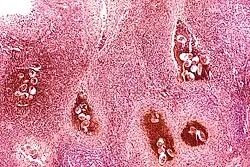

Rak urotelialny pęcherza moczowego, widoczne gniazda komórek nowotworowych

Rak urotelialny pęcherza moczowego

Inwazja warstwy mięśniowej raka urotelialnego

Ponad 90% przypadków raka pęcherza moczowego u ludzi stanowi rak urotelialny[65][66][67]. Rzadziej spotyka się rak płaskonabłonkowy dotyczący poniżej 5% przypadków tej choroby oraz gruczolakorak (rak gruczołowy) występujący u poniżej 2% chorych[67]. Preferuje się stosowanie terminu rak urotelialny zamiast rak przejściowokomórkowy[68]. Nowotwory pęcherza moczowego mogą wykazywać się brodawkowatym lub płaskim oraz nieinwazyjnym albo inwazyjnym typem wzrostu[69]. Około 75% raków pęcherza moczowego w momencie rozpoznania jest nieinwazyjna, czyli nie nacieka błony mięśniowej pęcherza moczowego (stadia Ta i T1 w klasyfikacji TNM), a pozostała część wykazuje inwazyjny typ wzrostu i wymaga odmiennego postępowania[70][71].

Inwazyjny (naciekający) rak urotelialny jest definiowany jako obecność inwazji nowotworowej poniżej błony podstawnej urotelium[74]. Makroskopowo inwazyjne nowotwory urotelialne mogą przyjmować formę brodawkowatą, polipowatą, guzkową, litą, tworzyć rozlany naciek ściany pęcherza moczowego. Zmiany mogą występować pojedynczo lub wieloogniskowo[75]. Typowo większość guzów pT1 jest brodawczakowata o niskim lub wysokim stopniu złośliwości histologicznej, z kolei guzy o większym zaawansowaniu pT2–T4 wykazują morfologię niebrodawczakowatą i cechują się wysokim stopniem złośliwości[76][77].

Mikroskopowo w utkaniu obecne są komórki tworzące gniazda, sznury komórek lub pojedyncze komórki pooddzielane desmoplastycznym podścieliskiem[76][78]. Możliwy jest bardziej rozlany wzór wzrostu nowotworu, w którym komórki tworzą arkusze, przy czym również w takim utkaniu spotyka się ogniskowo występujące gniazda komórek[78]. Komórki cechują się umiarkowaną do obfitej ilością amfofilnej lub eozynofilnej cytoplazmy i dużym hiperchromatycznym jądrem komórkowym. Jądra komórkowe wykazują znaczną pleomorficzność, nieregularne, kanciaste granice. Liczba i wygląd jąderek wykazuje znaczną zmienność. Gniazda komórek nowotworowych zwykle indukują reakcję desmoplastyczną podścieliska. Obecne są liczne figury mitotyczne i możliwa jest obecność nieprawidłowych figur mitotycznych. W podścielisku większości guzów jest obecny naciek limfocytów i komórek plazmatycznych, naciek najczęściej jest wyrażony ogniskowo od łagodnego do umiarkowanego stopnia, ale może być nasilony i rozlany[76][78]. Może być widoczna inwazja naczyń[78].